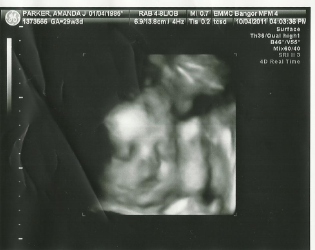

I went up to Bangor for yet another U/S. The report they gave my doctor before told about a "bulky placenta" and low amniotic fluid which is why my doc wanted to get another one. Also in the report everything else looked fine and normal. They did say they didn't get very good profiles and spine. The tech spent time measuring bones like the femur and upper arm. Both were a little over 5 inches. She also spent a good amount of time looking at the cervex, measuring fluid, checking out the placenta, making sure the kidneys were okay, the spine and great profile pics. After about an hour and half we were finally finished. I was getting a little uncomfortable laying on my back and also it was so quite that I was tired and wanted to sleep. We finished up and the tech sent in the doctor over the findings. She did say everything looks good including the placenta which has a couple bulky spots. The only thing not very good is that my fluid is still a little low. She said to make sure I keep hydrated and that I'll need to seen ever 2-3 weeks to make sure everything is okay. Then I was on my way. I've been really good about drinking my water and was doing at least 8 cups of day of water and whatever else liquids. Since my apt I've upped it up to at least 10 cups a day. I pee all the time! But I notice and like the feeling of drinking it. I have another apt on the 24th with my regular dr and I'm sure he'll go over the report and see where we go from here. I'm a little nervous because I'm hoping everything is okay with low fluids, but as long as I feel the baby kick I feel assured. They did however find in the u/s that our baby has hair already, she was weighing in at 3lb 1 oz which is average, she has cute, chubby cheeks, and when they zoomed in her nose and lips they looked just like Jaycee's. I do have pics that I'll post tomorrow.